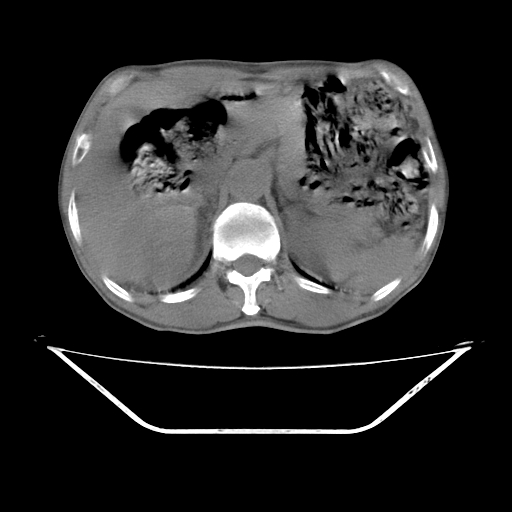

平扫

增强

考虑右肾盂癌,肾动脉受侵,右肾功能减退,右肾盂输尿管积水,管壁增厚,考虑种植转移,应该把下面扫完的

支持右侧肾盂癌伴肾静脉瘤栓形成可能性大,右肾结石.肝右叶后段低密度影,不除外转移.

考虑右肾盂癌,肾动脉受侵,右肾功能减退,右肾盂输尿管积水,管壁增厚,考虑种植转移  支持

考虑右侧肾盂癌。右侧输尿管扩张未扫描完。

右肾盂癌,肾动脉受侵,右肾盂输尿管积水,管壁增厚,考虑种植转移

右肾盂移行细胞癌并右输尿管中段转移.肾积水.

支持 右侧肾盂癌伴肾静脉瘤栓形成可能性大,右肾结石;肝右叶后段低密度影,不除外转移。

1.右侧肾盂癌伴肾盂积水。

3.右侧上段输尿管扩张,原因:(1)积水所致;(2)种植。